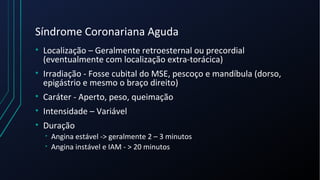

Dor torácica pode ter diversas causas, incluindo cardíacas como síndrome coronariana aguda, dissecção de aorta e pericardite, e não cardíacas como problemas pulmonares, musculoesqueléticos e do trato gastrointestinal. É importante avaliar a história clínica, características da dor e exame físico para identificar a possível causa e orientar o tratamento adequado.